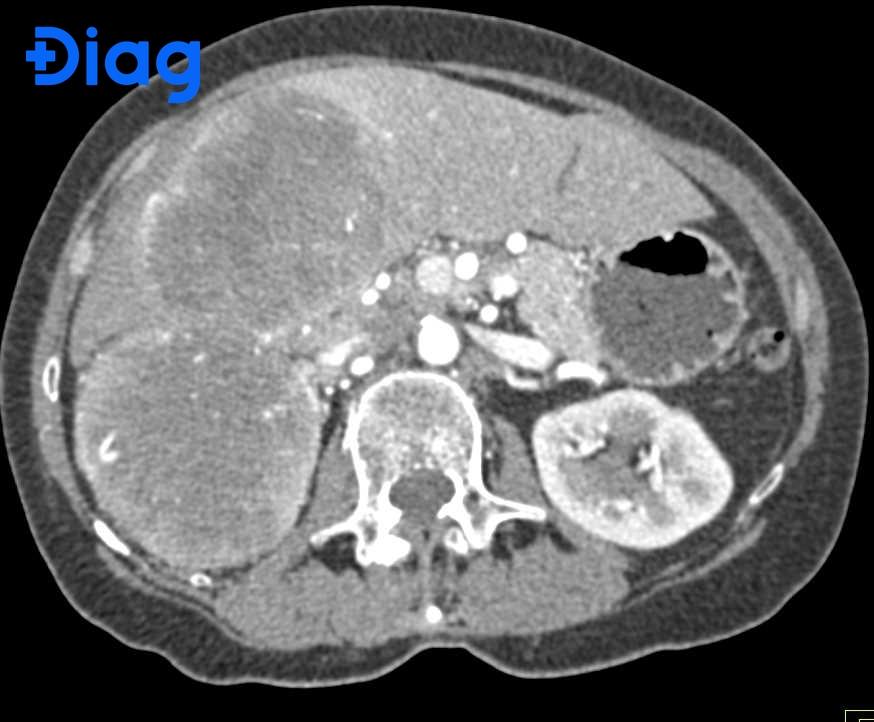

Để chẩn đoán u gan đa ổ, bác sĩ thường bắt đầu bằng các xét nghiệm máu, đặc biệt là với nồng độ AFP, vì khi nồng độ này cao có thể gợi ý tới ung thư gan. Siêu âm ổ bụng là kỹ thuật cận lâm sàng đầu tiên giúp khảo sát tình trạng gan, tiếp theo có thể là chụp cắt lớp vi tính (CT) hoặc chụp cộng hưởng từ (MRI) để xác định rõ hơn về các khối u.

Ngoài việc xác định tính chất lành tính hay ác tính của khối u, chẩn đoán cũng cần đánh giá chức năng gan thông qua các xét nghiệm liên quan. Việc hiểu rõ về tình trạng gan sẽ giúp bác sĩ quyết định phương pháp điều trị hiệu quả nhất, có thể bao gồm phẫu thuật, hóa trị hay phương pháp đốt khối u bằng sóng cao tần.